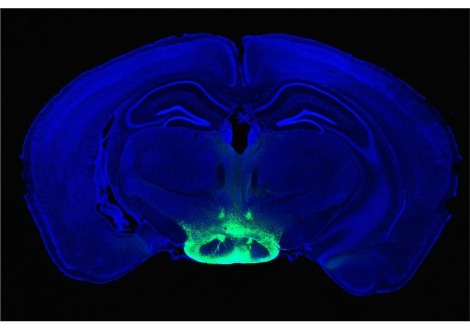

أظهر المشاركون عند تعرّضهم للتعب نشاطاً دماغيّاً أكبر في منطقتي القشرة الكمثريّة piriform cortex و القشرة الجبهية الحجاجية orbitofrontal cortex المشاركتان في الاستجابة الشميّة للروائح، في حين لم يُظهر المشاركون هذا النشاط عندما نالوا قسطاً كافياً من الرّاحة. تقول المؤلفة المشاركة "سورابهي بوتاني" من جامعة الشمال الغربي في مدرسة فينبرغ للطب في شيكاغو بأنّ هذا الارتفاع لم يظهر عند الاستجابة للروائح غير الغذائية.